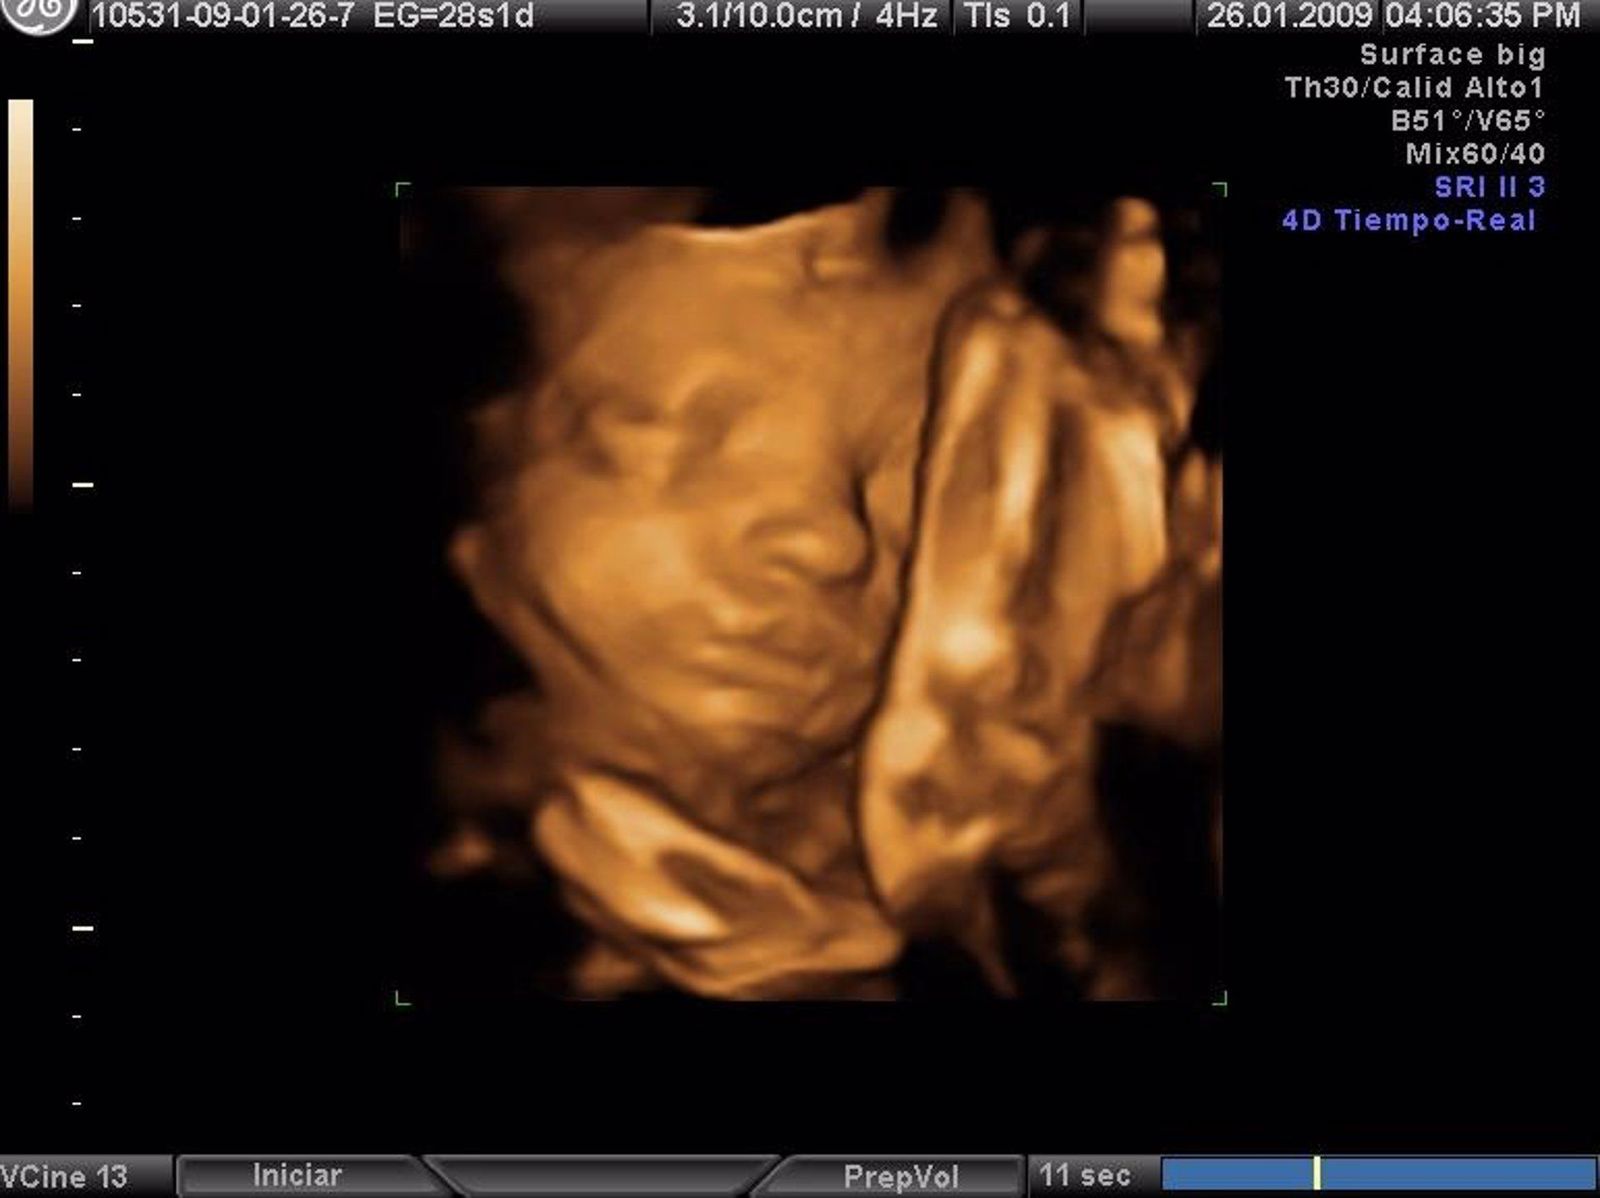

Ecografía en una foto de archivo de Europa Press.   EUROPA PRESS   Archivo